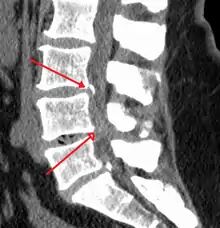

The diagnosis of spinal stenosis involves a complete evaluation of the spine. The process usually begins with a medical history and physical examination. X-ray and MRI scans are typically used to determine the extent and location of the nerve compression.

MRI has become the most frequently used study to diagnose spinal stenosis. The MRI uses electromagnetic signals to produce images of the spine. MRIs are helpful because they show more structures, including nerves, muscles, and ligaments than seen on X-rays or CT scans. MRIs are helpful in showing exactly what is causing spinal nerve compression.